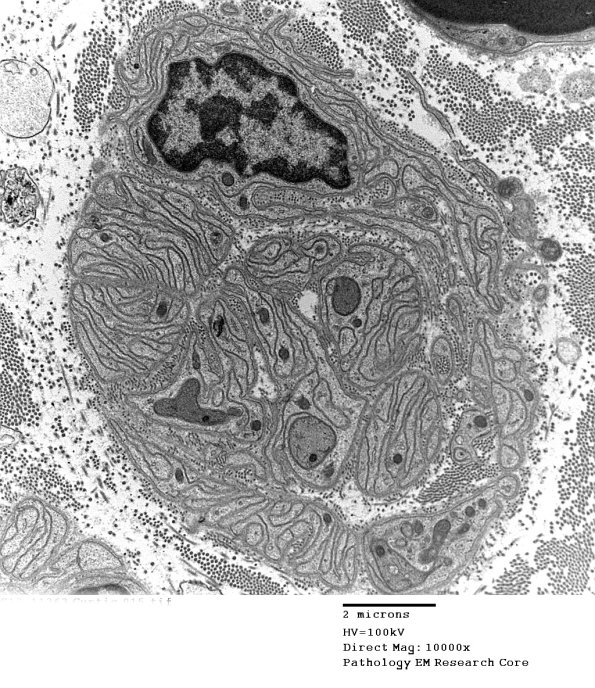

4B1,2 In most cases the Schwann cell processes form long stacked aggregates.